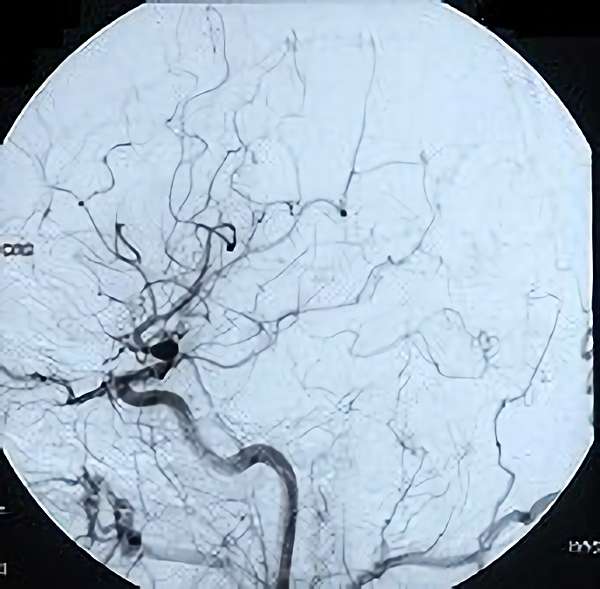

脳血管撮影

手術前

手術後

全治。

脳血管撮影により完全除去が確認された